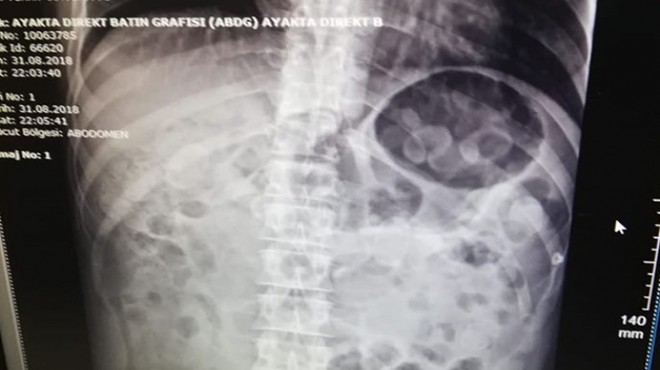

Zanlının hastanede röntgen filmi çekilerek yapılan kontrollerinde, midesinde uyuşturucu taşıdığı anlaşıldı.

Zanlının midesinden istifra yoluyla ve dışkısından siyah elektrik bandına sarılmış kapsül halinde metamfetamin maddesi çıktı.

Toplam 198 gram ağırlığında uyuşturucuyu midesinde sakladığı belirlenen zanlı, gözaltına alınarak Narkotik Suçlarla Mücadele Şube Müdürlüğüne götürüldü.